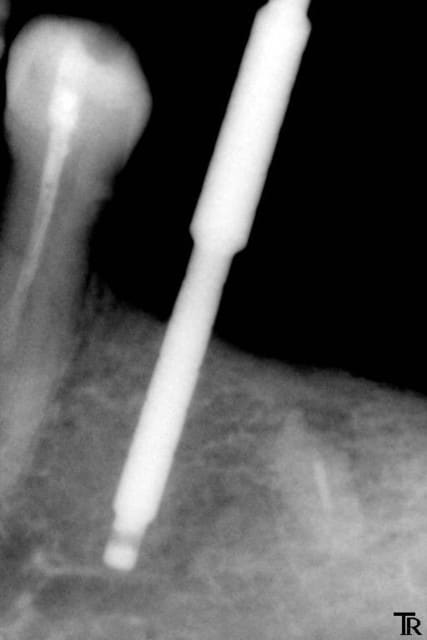

Je suis de nature très prudent, je fore à 12mm. Radio de contrôle, je suis tangent au canal dentaire. Le Kontact doit être mis en sous crestal, même avec le 4.2X10 je ne veux pas faire prendre de risque à ma patiente. Je décide donc de poser un smilea conic à 4.4X10, que je pourrai poser en juxta.

Je réalise toute la séquence opératoire. Je mets des stops à sur tous mes forêts à 10 mm.

Je mets l’implant en place, et voilà ce que j’obtiens après la radio : l’implant qui aurait pu être mis plus profondément.

1  ere jauge ekl1xk - Eugenol